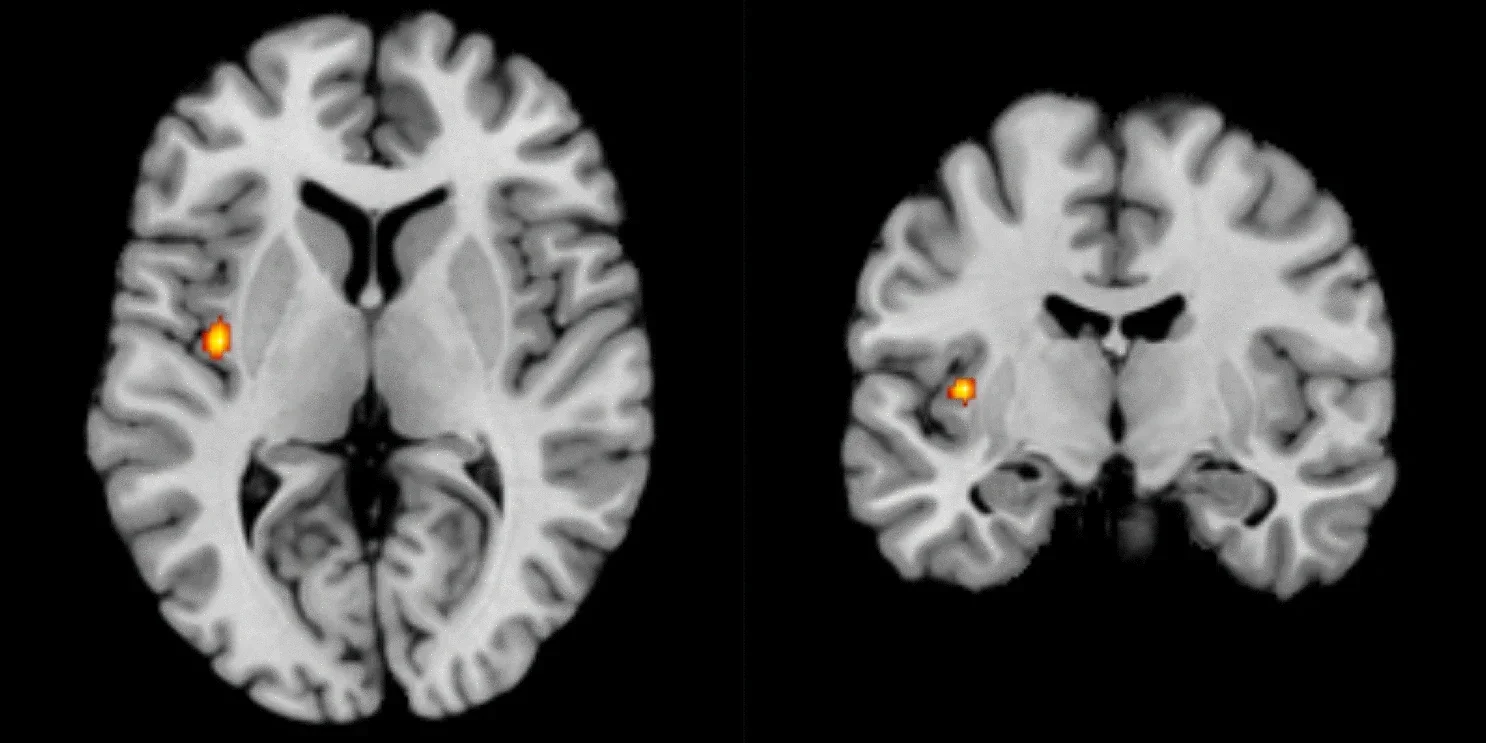

El descubrimiento no se queda en la nariz. Las neuronas olfativas proyectan sus axones —los canales de salida de información de las neuronas— hacia el bulbo olfatorio, la primera estación de procesamiento en el cerebro. Allí, las neuronas que expresan el mismo receptor convergen en estructuras llamadas glomérulos.

El nuevo estudio demuestra que la posición de los receptores en la nariz está alineada con la posición de esos glomérulos en el cerebro. Es decir, el mapa olfativo periférico y el central están coordinados.

Esta correspondencia resuelve un problema clásico de la neurociencia: cómo logra el sistema olfativo organizar con precisión miles de tipos de señales diferentes. La respuesta es que esa organización ya está preconfigurada en la propia nariz.